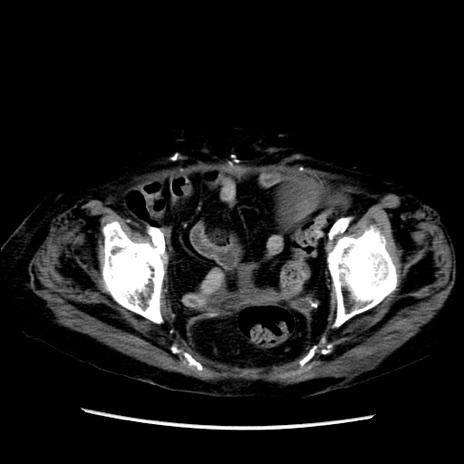

症例14(横断像)

【症例】 90歳代女性

【主訴】 腹痛・嘔吐

【現病歴】今朝から左側腹部痛を認めた。 経過観察していたが、嘔吐を認めたため来院。

【既往歴】 子宮癌術後

【身体所見】 意識清明、BP 127/54mmHg、P 98bpm Sp02 95%(RA)、BT 35.8°C、腹部平坦・軟腸ぜん動音聴取良好、右下腹部圧痛(+) 反跳痛なし

【データ】WBC 9800、CRP 0.46